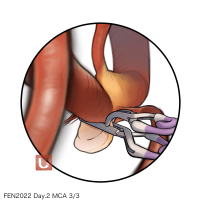

FEN2022シリーズ